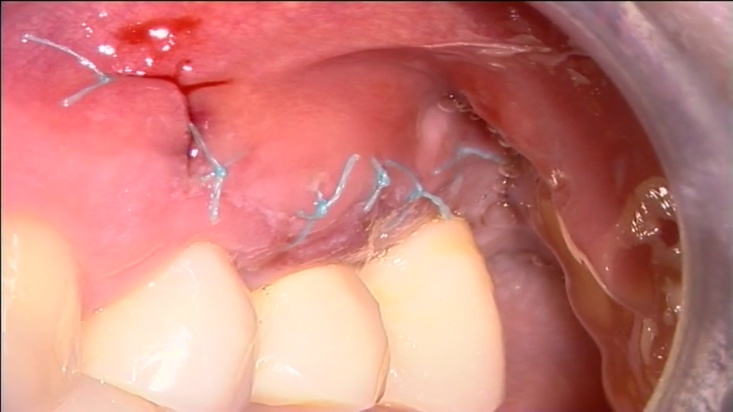

Сл. 27.69

Сл. 27.69 Хируршка терапија на латерална лезија. а) Предоперативна радиографија на максиларен лев втор премолар. Латерална лезија е присутна. б) Преку хируршки флап, латералниот канал одговорен за лезијата бил оптуриран со супер-EBA. в) Постоперативна радиографија. г) Контрола по две години покажува оптурација на латералниот канал и комплетно заздравување на латералната лезија.